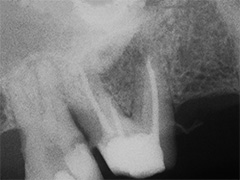

Aufbissempfindlichkeit an 33 veranlasste uns erstmalig in dieser Kieferregion zu röntgen. Mit grossen Augen sahen wir dann an, was uns auch ansah. Einen Knochendefekt dieser Grössenordnung mit seiner schaurigen Aura sieht man zum Glück nicht jeden Tag. Doch, obgleich das Alien dereinst Zahn 34 entsprang, war eine Behandlung nur am Zahn davor durchsetzbar. Dessen Wurzelfüllung erfolgte regulär nach 14 Tagen, neue Terminangebote aber wurden, weil angeblich nicht mehr nötig, verschmäht.

Keine 8 Wochen gingen noch in's Land, bis das mit Macht geschah, was lange schon erwartet war. Das Arbeitsprogramm bestand aus Eröffnung von Zahn 34 und einer Schwellung inkl. Drainage, am nächsten Tag dann noch Aufbereitung des Kanals mit Einlage. 2 Wochen später dann die Füllung plus einem als Resektion deklarierten Auslöffeln des Granu­lationsgewebes durch eine Mini-Öffnung, zu deren Verschluss eine Naht genügte.

3 Aufnahmen sind von 2001, die vierte vom Nov. 2006